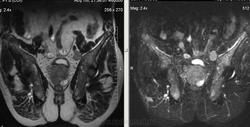

Метастазы рака простаты, кроме измений в позвонках видна сама первичная опухоль и лимфатические узлы (общий и наружный подвздошные слева, ещё один в левой подвздошной ямке).

После добавления томограмм исследования органов малого таза картина стала ещё печальнее...

Да, запустил пациент. До этого были проблемы с мочеиспусканием, рези, болезненность. Лечился самостоятельно от простатита, отмечал временное улучшение.